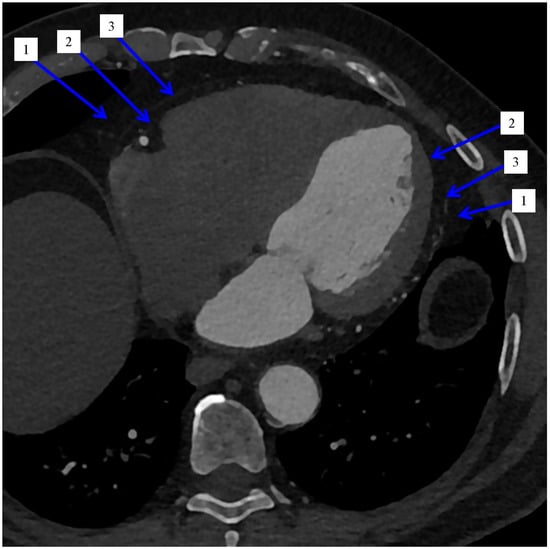

2.2. Imaging and Measurement Methods of Epicardial Adipose Tissue